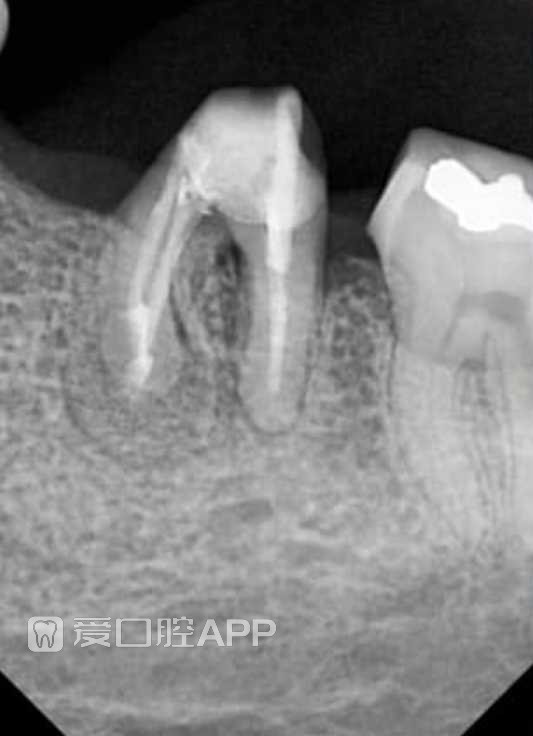

看个难搞的牙 —— 下颌第一磨牙 附一年随访